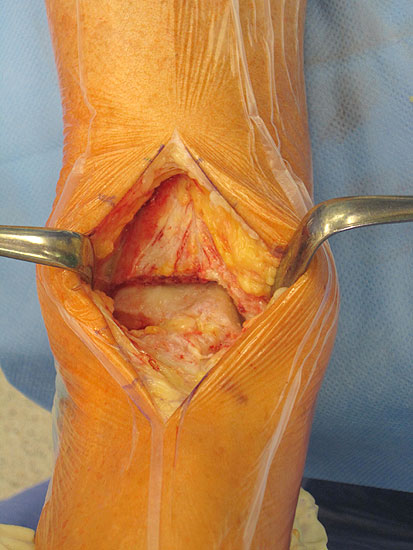

• Gefahren

1. Wundheilungsstörung infolge einer hohen intraoperativen Druck- und Zugbelastung auf den periartikulären Weichteile; Lösung: dosierte Weichteilbehandlung durch die Hacken durch den Assistenten; aktive Erinnerungen während der Operation (Abb. 20 und 21)